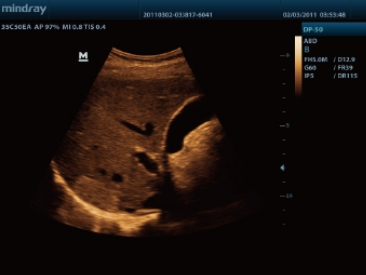

3D 胎儿面部